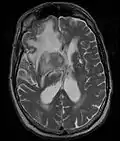

- Primary CNS Lymphoma

MRI T1 Axial

MRI T1 Axial MRI T1 Coronal

MRI T1 Coronal MRI T1 Sagittal

MRI T1 Sagittal MRI T2 Axial

MRI T2 Axial

- Restricted to brain, CSF, eyes, or rarely spinal cord

- Clinicopathologic variants include intracranial lesions, diffuse leptomeningeal or periventricular, vitreous, and spinal lesions.

- Intracranial primary CNS lymphoma are generally 75% supratentorial and 25% infratentorial.

- Primary CNS lymphoma is multifocal in 50% of AIDS-related variants, and multifocal in 25% of immunocompetent variants.

- MRI significantly underestimates extent of involvement; May appear focal on CT or MRI but parenchyma is typically diffusely involved.

- Intensely enhancing on MRI; may have a diffuse or “cotton wool” appearance on imaging.

- Classified as Stage IE NHL, because they are typically restricted to a single extranodal site